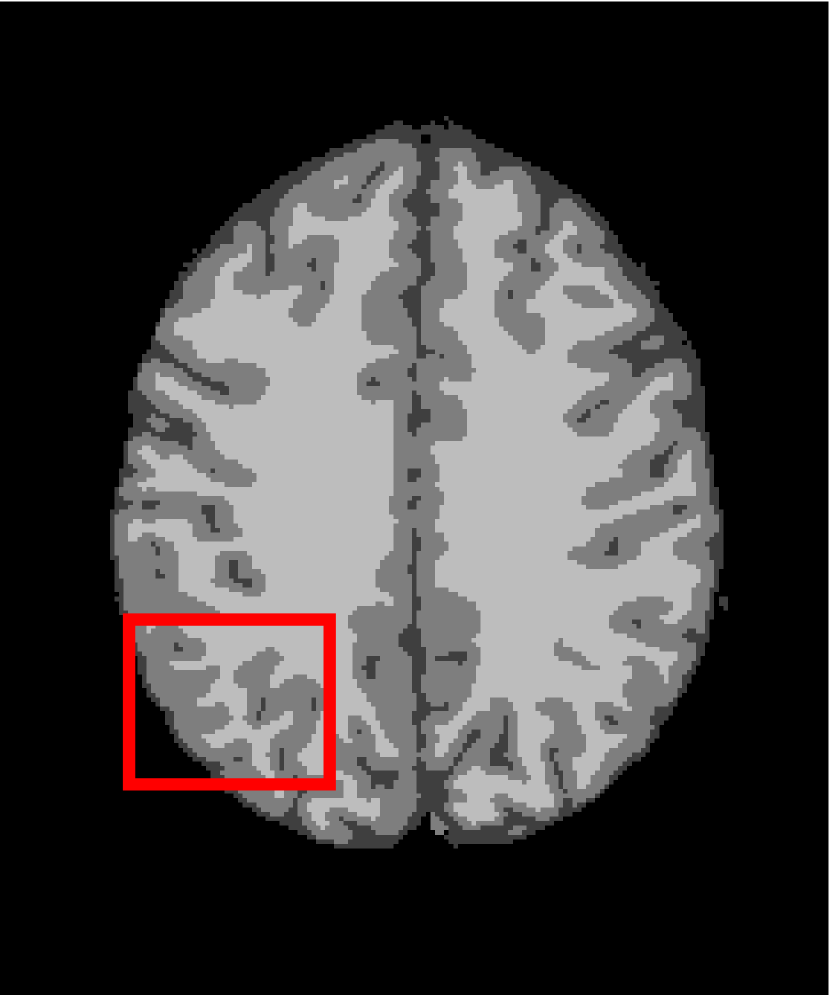

In the second experiments, we segment two medical images coming from a simulated brain database (BrianWeb): http://www.bic.mni.mcgill.ca/brainweb/. The two images are generated by T1 modality with slice thickness of 1mm resolution, 9% noise and 20% intensity non-uniformity. Here, the two images are represented two slices in the axial plane with the sequence of 100 and 110. Moreover, there are golden standard segmentations in the dataset. We set the numbers of clusters to 4. The visual comparisons are illustrated in Figs. 6 and 7.

Figure 7: Segmentation results for the second medical image. From (a) to (l): ground truth, noisy image and results of FCM_S1, FCM_S2, FGFCM, FLICM, KWFLICM, ARKFCM, FRFCM, WFCM, DSFCM_N, and LRFCM.

By focusing on the marked red square in Figs. 6 and 7, we easily find that FCM_S1, FCM_S2, FGFCM and ARKFCM are sensitive to noise. FLICM and KWFLICM are vulnerable to severe intensity inhomogeneity. FRFCM brings overly smooth results due to the use of gray level histograms. WFCM and DSFCM_N cause several contours to change. However, LRFCM acquires clear contours and suppresses noise adequately. Moreover, we find that the segmentation result of LRFCM is closer to ground truth.